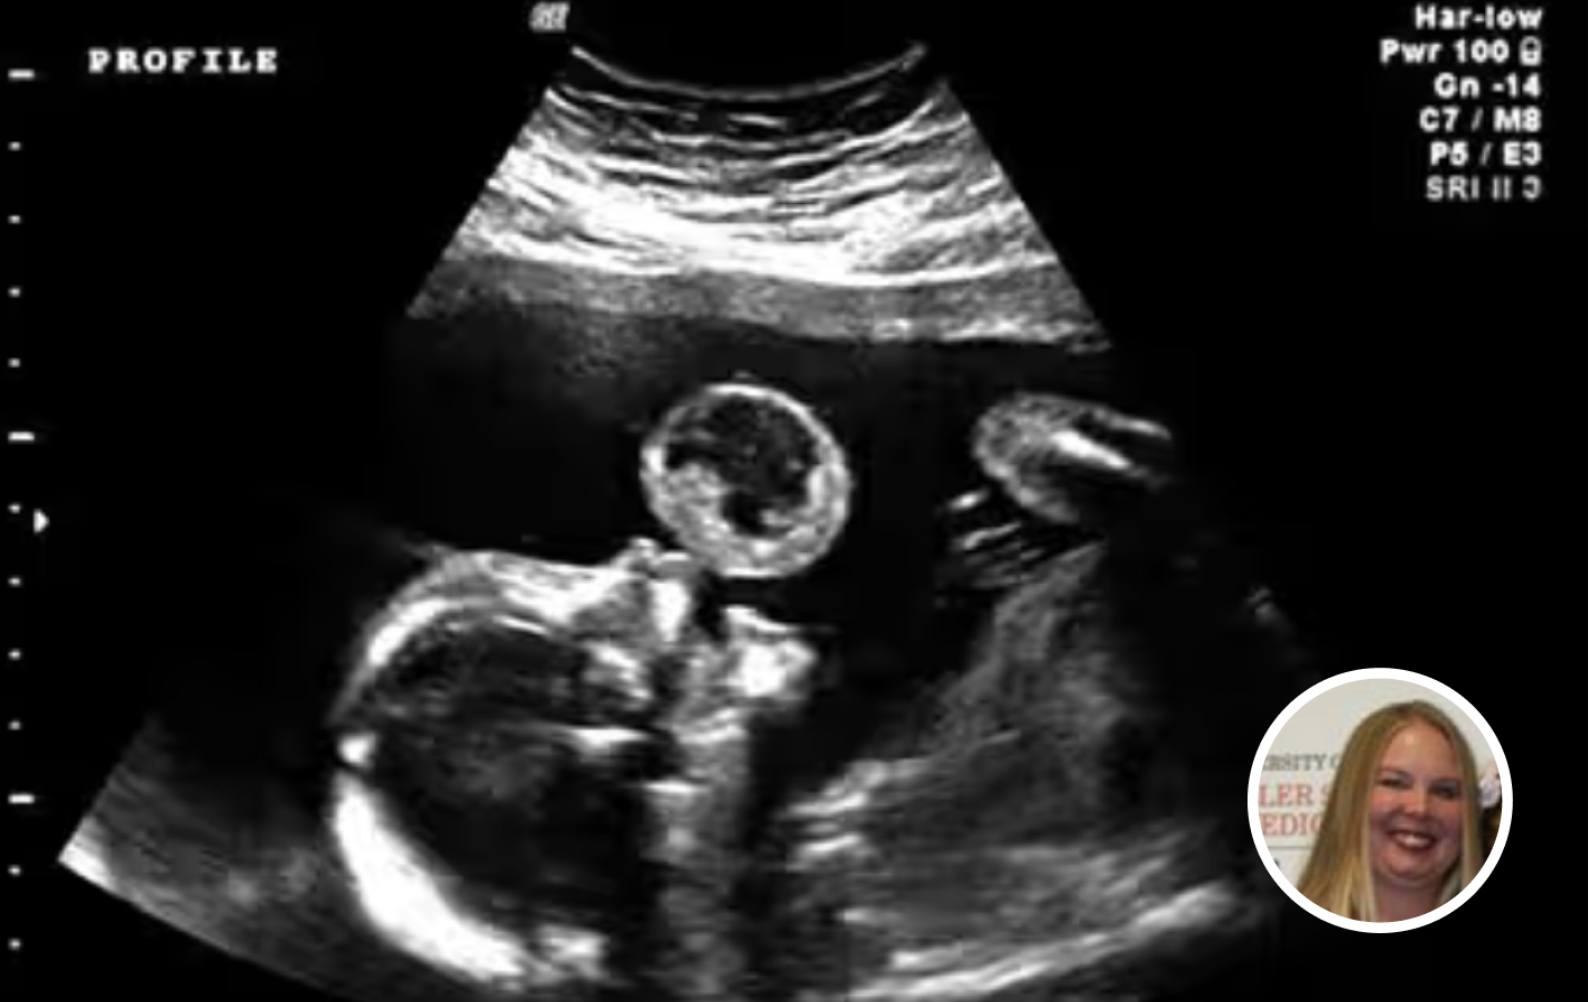

Tammy Gonzalez, a Miami resident, was expecting her baby when she went in for a standard ultrasound—a moment many mothers anticipate with joy, as they catch the first glimpse of their child. But during this appointment, doctors noticed something alarming. Hovering just above the baby’s mouth was what appeared to be a large, translucent bubble.

“Is that on me or the baby?” Gonzalez recalls asking the technician, trying to make sense of what she was seeing.

After further analysis, the bubble was diagnosed as a teratoma—a rare and often life-threatening tumor that can develop in utero. These tumors are seen in approximately 1 in every 100,000 births and can grow rapidly, threatening the baby’s ability to survive. The news was devastating. Doctors warned Gonzalez of the risks: not only could the tumor lead to miscarriage, but continuing the pregnancy could also endanger her own health. The medical recommendation was clear—termination.